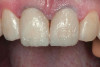

(12.) Postoperative upper anterior view.

Figure 12

After the composite veneers were finalized, impressions were taken for a monolithic lithium disilicate crown on tooth No. 12. This was placed during a subsequent appointment, and occlusal equilibration was carried out. The patient returned for final photographs a couple of weeks later (Figure 10 through Figure 14).

During subsequent appointments, teeth Nos. 4 through 13 were restored with direct composite veneers in stages. Teeth Nos. 6 through 12 were treated first, followed by teeth Nos. 4, 5, and 13, respectively. Lingual and facial silicone putty indices were fabricated from the wax-up (Figure 7), and the lingual matrix was marked with a sharp probe at the existing incisal edge. Next, low-pressure air abrasion was used to clean the area and roughen the enamel to be bonded. Teeth Nos. 4 and 12 were isolated using polytetrafluoroethylene plumber's tape, and a 37.5 % phosphoric acid etching gel was applied and rinsed off. A layer of a fifth-generation bonding agent was applied and air-thinned, then a second layer was applied, air-thinned, and cured. The application of two layers has been shown to produce an increase in microtensile bond strength.20 After placement of the bonding agent, a clear enamel shade of microhybrid composite was applied into the lingual matrix in a thin layer and drawn slightly over the previously marked line. The composite was thickened toward the facioincisal line angle, which creates a natural "halo effect." The matrix was then adapted to the teeth, and the lingual shelf was briefly cured (Figure 8).

Any excess composite on the lingual surface of the teeth was removed before the lingual shelf was fully cured. Next, a microhybrid composite in a dentin shade was layered onto the teeth and the lingual shelf, drawn out into mamelon shapes with the aid of a sable brush, and fully cured. Using a hybrid composite for the lingual shelf and dentin layer provides wear resistance and strength for the restoration.21,22 Next, a small amount of material in a translucent blue shade was used in between and around the previously created mamelons in order to "lock in" the natural translucency and create a lower value appearance between the dentinal lobes (Figure 9). Finally, a layer of microfill in shade B1 was applied to full contour and cured. A matrix pull-through technique was used in the interproximal areas. Final curing was performed after the application of a glycerin gel to ensure a fully cured restoration surface. The decision to use a microfill in the visible areas that would not be placed under occlusal load was based on its superior polishability.22 A similar incremental layering technique was used on the cuspids and bicuspids.

With the patient sitting up, the incisal edges were finished parallel to the interpupillary line. After placing the patient back into a supine position, refinement of the primary anatomy was carried out with a fine grit, flame-shaped diamond bur. Coarse discs were then used to shape the cervical, middle, and incisal facial contours and open the incisal embrasures. The facioincisal line angles were marked with a pencil to ensure that proper placement was maintained during the shaping and finishing procedure. The proximal line angles, which were also marked with a pencil, were finished using medium coarse discs to establish light reflecting and light deflecting areas.

Once the primary anatomy was finished, secondary anatomy was created by first marking off the desired position of developmental grooves with pencil and then placing them carefully with a flame-shaped diamond bur and abrasive points. The patient was also fitted with a bleaching tray for the lower arch and instructed to bleach only the lower anterior teeth.

The final polish was performed using a series of fine grit discs in various sizes, and a glass-like luster was achieved by applying aluminum oxide polishing paste with felt discs and points under light pressure.